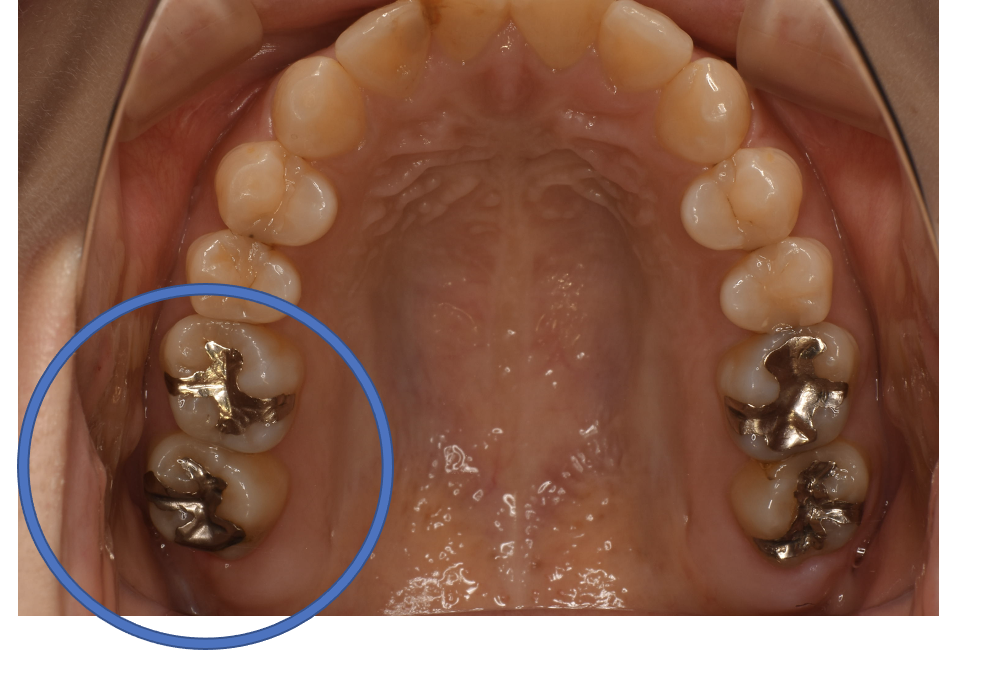

Before

| 備考 | 院長より 銀歯の内部に虫歯が進行してしまっていたケースです。中を開けて見てみると、外から想像するよりもはるかに虫歯が広がってしまっていました。幸運にも神経を保存できたので、生きた臓器としてまだ使うことが可能です。残存歯質がかなり薄く弱くなってしまったので、ジルコニアで被せて守ってあげています。しっかりとした治療ができたので、まだまだ長く使っていけるでしょう。 |